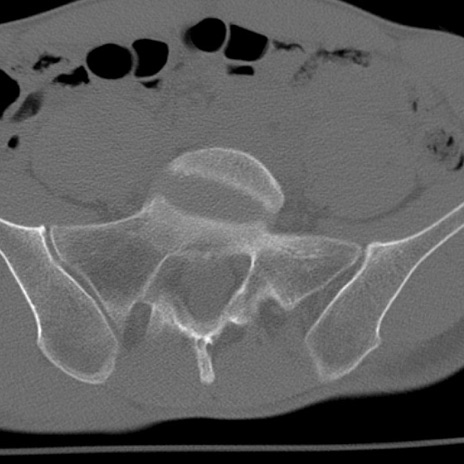

症例3 腰椎CT(横断像)

腰椎CT